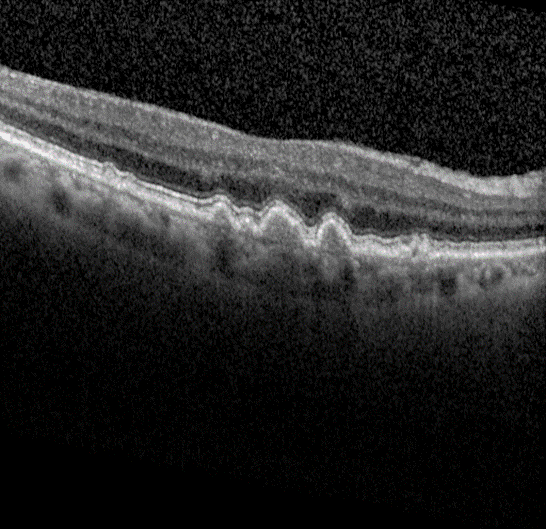

Advanced form of age-related macular degeneration (AMD) is a major health burden that can lead to irreversible vision loss in the elderly population. For early preventative interventions, there is a lack of effective tools to predict the prognosis outcome of advanced AMD because of the similar visual appearance of retinal image scans in the early stage and the variability of prognosis paths among patients. An early characteristic of AMD is drusen, which appears as yellowish deposits under the retina (Figure 1 left). AMD is mainly categorized into two types: Dry AMD (non-neovascular, Figure 1 middle) is represented by drusen deposition, later evolving into confluent areas of regressed drusen and ultimately in the advanced dry stage presenting as loss of vision associated with retinal pigment epithelium (RPE) atrophy (clinically known as geographic atrophy, GA). Wet AMD (neovascular, Figure 1 right) is characterized by the leakage of fluid in the sub-RPE and subretinal spaces caused by neovascularization. The overall objective for this study is to design, develop, and evaluate AMD prognosis prediction models that can detect most relevant images containing AMD biomarkers, manage unevenly spaced sequential optical coherence tomography (OCT) images and predict all advanced AMD forms that can help with the interpretation and explainability of computer-aided prognosis models. Read more

Figure 1: Dursen (left), Dry AMD (middle) and Wet AMD (right)